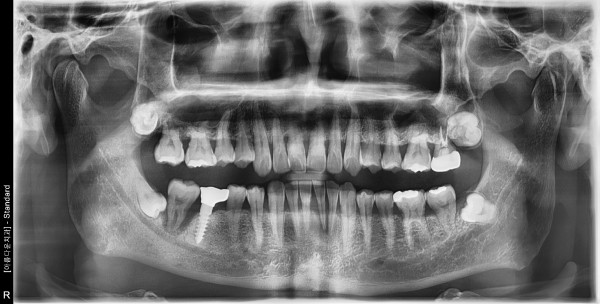

47세남자 우측구치부.하악전치부 뼈이식및임플란트식립